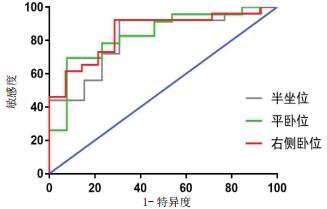

2.3 胃窦截面积对肠内营养喂养不耐受的预测价值根据喂养不耐受诊断标准,本研究危重患者在肠内营养期间喂养耐受者27例、喂养不耐受者15例。其中,喂养不耐受者在半坐位、平卧位及右侧卧位时的胃窦截面积值分别为(8.53±4.07)cm2、(5.15±2.75)cm2、(10.32±4.06)cm2,喂养耐受者在相应体位时的胃窦截面积值分别为(4.60±2.76)cm2、(2.61±1.32)cm2、(4.95±3.20)cm2;与喂养耐受者相比,喂养不耐受者三种体位胃窦截面积值均显著增加,组间比较差异均有统计学意义[均P < 0.005]。ROC分析显示,危重患者在半坐位检测时,胃窦截面积预测喂养不耐受的ROC曲线下面积为0.815,以≥3.917 cm2为截点时的敏感性为92.0%、特异性为69.2%;在平卧位检测时,胃窦截面积预测喂养不耐受的ROC曲线下面积为0.833,以≥3.395 cm2为截点时的敏感性为69.6%、特异性为92.3%;在右侧卧位检测时,胃窦截面积预测喂养不耐受的ROC曲线下面积为0.849,以≥4.402 cm2为截点时的敏感性为92.3%、特异性为71.4%。见图 3。

| 图 3 不同体位超声测量胃窦截面积预测喂养不耐受的ROC曲线 Fig 3 ROC curves of gastric antrum cross-sectional area in predicting feeding intolerance by ultrasound under different body positions |

肠内营养不仅能为危重患者补充足够的营养物质,还利于维护胃肠道结构与功能的完整性、降低肠道渗透性及改善免疫系统功能等,进而促进胃肠功能障碍的恢复,已成为危重患者的重要治疗[13]。目前的营养治疗指南建议,危重患者若不存在肠内营养治疗的禁忌,应在入院24~48 h内实施肠内营养支持治疗[14]。然而,危重患者的胃肠功能障碍可能导致肠内营养期间喂养不耐受的发生,进而增加胃潴留甚至反流、误吸的风险。因而,在肠内营养实施的过程中,需要进行胃残余量监测,以实时辅助评估患者喂养不耐受的发生及进行肠内营养治疗方案的调整,为患者最大程度地实现充分的肠内营养治疗。本研究发现床旁超声能较为准确地反应胃残余量,在此基础上进一步分析了其对肠内营养喂养不耐受的预测价值。结果显示,危重患者在半坐位、平卧位及右侧卧位等三种体位下,进行超声检测获得的胃窦截面积预测肠内营养喂养不耐受的ROC曲线下面积分别为0.815、0.833、0.849,提示三种体位下的检测结果均能预测喂养不耐受的发生,其中右侧卧位下检测值的敏感性与特异性最佳,预测效果最好。因而,床旁胃超声检测可作为危重患者肠内营养喂养不耐受的有效预测工具。